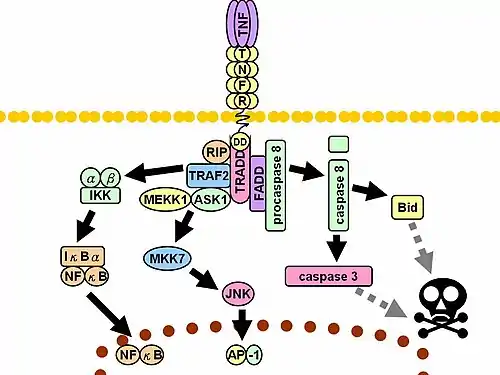

Cell signaling

TNF can bind two receptors, TNFR1 (TNF receptor type 1; CD120a; p55/60) and TNFR2 (TNF receptor type 2; CD120b; p75/80). TNFR1 is 55-kDa and TNFR2 is 75-kDa.[40] TNFR1 is expressed in most tissues, and can be fully activated by both the membrane-bound and soluble trimeric forms of TNF, whereas TNFR2 is found typically in cells of the immune system, and responds to the membrane-bound form of the TNF homotrimer. As most information regarding TNF signaling is derived from TNFR1, the role of TNFR2 is likely underestimated. At least partly because TNFR2 has no intracellular death domain, it shows neuroprotective properties.[32]

Upon contact with their ligand, TNF receptors also form trimers, their tips fitting into the grooves formed between TNF monomers. This binding causes a conformational change to occur in the receptor, leading to the dissociation of the inhibitory protein SODD from the intracellular death domain. This dissociation enables the adaptor protein TRADD to bind to the death domain, serving as a platform for subsequent protein binding. Following TRADD binding, three pathways can be initiated.[41][42]

- Activation of NF-κB: TRADD recruits TRAF2 and RIP. TRAF2 in turn recruits the multicomponent protein kinase IKK, enabling the serine-threonine kinase RIP to activate it. An inhibitory protein, IκBα, that normally binds to NF-κB and inhibits its translocation, is phosphorylated by IKK and subsequently degraded, releasing NF-κB. NF-κB is a heterodimeric transcription factor that translocates to the nucleus and mediates the transcription of a vast array of proteins involved in cell survival and proliferation, inflammatory response, and anti-apoptotic factors.

- Activation of the MAPK pathways: Of the three major MAPK cascades, TNF induces a strong activation of the stress-related JNK group, evokes moderate response of the p38-MAPK, and is responsible for minimal activation of the classical ERKs. TRAF2/Rac activates the JNK-inducing upstream kinases of MLK2/MLK3,[43] TAK1, MEKK1 and ASK1 (either directly or through GCKs and Trx, respectively). SRC- Vav- Rac axis activates MLK2/MLK3 and these kinases phosphorylate MKK7, which then activates JNK. JNK translocates to the nucleus and activates transcription factors such as c-Jun and ATF2. The JNK pathway is involved in cell differentiation, proliferation, and is generally pro-apoptotic.

- Induction of death signaling: Like all death-domain-containing members of the TNFR superfamily, TNFR1 is involved in death signaling.[44] However, TNF-induced cell death plays only a minor role compared to its overwhelming functions in the inflammatory process. Its death-inducing capability is weak compared to other family members (such as Fas), and often masked by the anti-apoptotic effects of NF-κB. Nevertheless, TRADD binds FADD, which then recruits the cysteine protease caspase-8. A high concentration of caspase-8 induces its autoproteolytic activation and subsequent cleaving of effector caspases, leading to cell apoptosis.

The myriad and often-conflicting effects mediated by the above pathways indicate the existence of extensive cross-talk. For instance, NF-κB enhances the transcription of C-FLIP, Bcl-2, and cIAP1 / cIAP2, inhibitory proteins that interfere with death signaling. On the other hand, activated caspases cleave several components of the NF-κB pathway, including RIP, IKK, and the subunits of NF-κB itself. Other factors, such as cell type, concurrent stimulation of other cytokines, or the amount of reactive oxygen species (ROS) can shift the balance in favor of one pathway or another. Such complicated signaling ensures that, whenever TNF is released, various cells with vastly diverse functions and conditions can all respond appropriately to inflammation. Both protein molecules tumor necrosis factor alpha and keratin 17 appear to be related in case of oral submucous fibrosis[45]